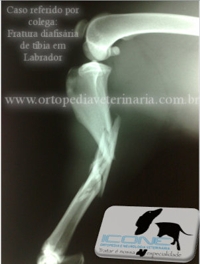

Fratura cominutiva de tíbia em Labrador. Colocação de Fixador Circular em abordagem fechada, permite apoio precoce com o mínimo dano adicional oa tecido ósseo.